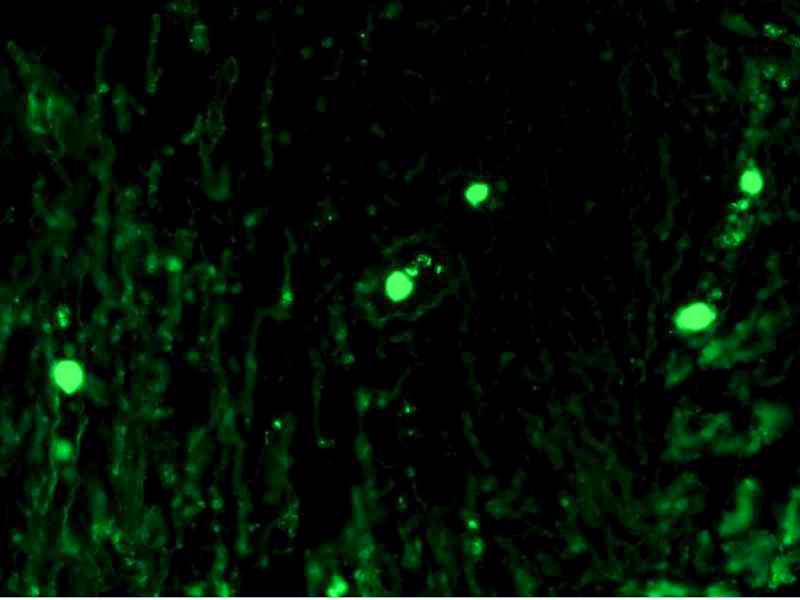

cf488 IgA 1 Published April 6, 2021 at 800 × 600 in cf488 IgA 1 Formalin fixed paraffin embedded human tonsil stained with IgM-CFTM488 cf488 IgA 1 ← Previous Next →